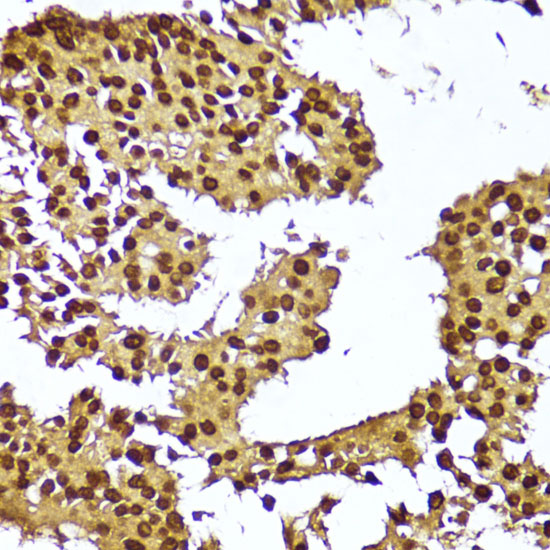

Immunohistochemistry of paraffin-embedded human breast cancer using TERT at dilution of 1:100 (40x lens).

IHC 1:50 - 1:200